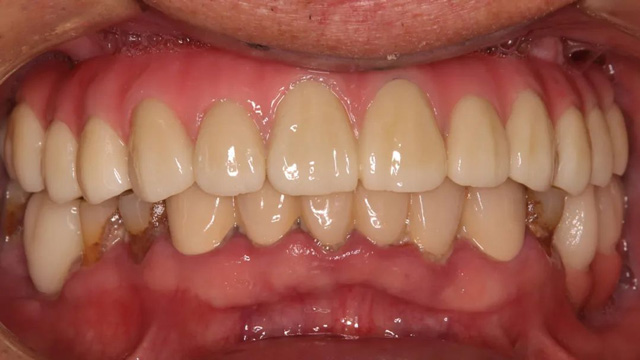

种植手术完成后,沈老师戴上了临时牙,上半口的咀嚼功能得到恢复,嘴巴也不再瘪瘪的了。看着镜子里那一排似曾相识的上牙,他感觉像做梦一样,回想起这几年所受的折磨,他感慨不已。

完成上半口戴牙后